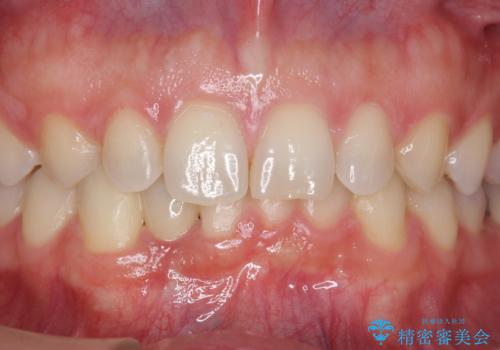

被せ物の色を決める前に、ホワイトニングを行なっています。

- 45万円(税別) 内訳:ストローマンインプラント(1本)20万円、ジルコニアクラウン10万円、シリンダーTeC 2万円 ジルコニアカスタムアバットメント10万円 ホワイトニング(エクセレント)3万円費用は治療当時の料金となります

唇側の骨増成もしっかり行い、前歯部インプラントによくある、歯茎が下がって見えることもない、審美的なインプラント補綴ができました。